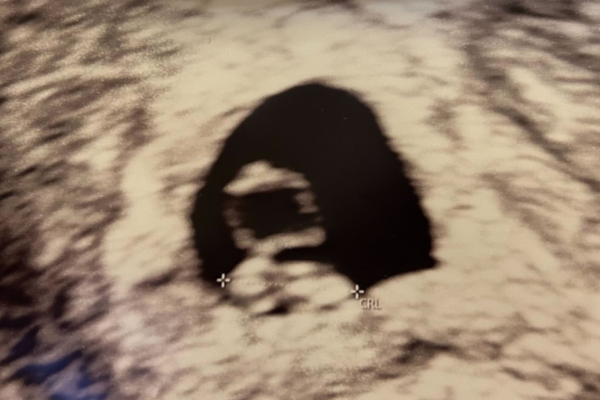

I løbet af denne uge vokser barnet fra 7-9 mm og vejer cirka 0,8 gram. Det lille hjerte slår sine første slag. Det kan tidligst ses på ultralyd fra 5+4, hvis I vælger at få en tidlig scanning. Det er en KÆMPE stor oplevelse at se, og måske høre barnets hjertelyd! På ultralyd kan man også se, om der er mere end ét barn.

Få en tidlig scanning. Det er bare helt igennem fantastisk at opleve babyen på en scanning og se hjerteblink, det fremmer jeres tilknytning til det lille barn og gør graviditeten mere virkelig. Læs mere her